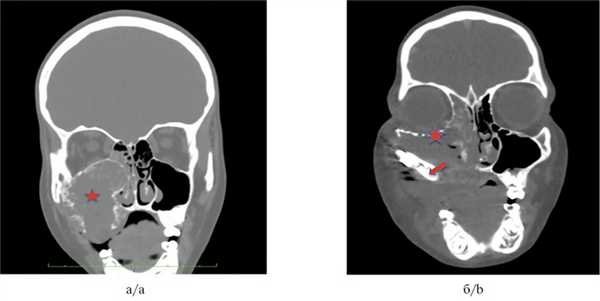

Для ЮПОФ характерен симптом «матового стекла», для ЮТОФ — хаотичное включение кальцинатов (рис. 1, а, 2, а) [9].

Рис. 2. Клинический случай 2. КТ, коронарная проекция.

а — ЮПОФ верхней челюсти с вовлечением и деструкцией альвеолярного отростка верхней челюсти справа. Звездочкой показано образование; б —снимки через 5 мес после максиллэктомии с микрохирургической реконструкцией верхней челюсти свободным малоберцовым гребнем. Послеоперационные изменения в проекции верхней челюсти, верхнечелюстная пазуха. Стрелкой показан трансплантат. Нет данных за рецидив.Дифференциальная диагностика проводится прежде всего с фиброзной дисплазией (ФД), ее бывает затруднительно выполнить морфологически, однако рентгенологически, как правило, визуализируются выраженные различия: при ЮОФ образование четко отграничено от прилежащей кости, при ФД отсутствует демаркационная разграничительная зона от здоровой кости, образование распространяется вдоль костных анатомических структур, повторяя конфигурацию вовлеченной кости [11—12]. В связи с этим диагноз ЮОФ должен ставиться комплексно, с учетом клинических, рентгенологических и морфологических данных [1—3].

Клинический случай № 2

Пациент, 8 лет, поступил в НМИЦ ДГОИ с жалобами на асимметрию лица за счет безболезненного выбухания в области правой щеки в течение 3 мес. По месту жительства пациенту проводилось лечение по поводу периостита верхней челюсти, далее была выполнена биопсия. При пересмотре материала в НМИЦ ДГОИ установлен диагноз: ЮОФ, псаммоматоидный тип. По данным КТ при поступлении: образование верхней челюсти слева, с вовлечением и разрушением альвеолярного отростка и верхнечелюстной пазухи.

Пациенту было произведено радикальное хирургическое лечение в объеме резекции левой верхней челюсти с микрохирургической реконструкцией свободным малоберцовым лоскутом, с одномоментной реконструкцией нижней стенки орбиты. По данным визуализации после операции: нет признаков резидуальной опухоли, трансплантат состоятелен.

На рис. 2 представлены КТ-снимки пациента до и после хирургического лечения.